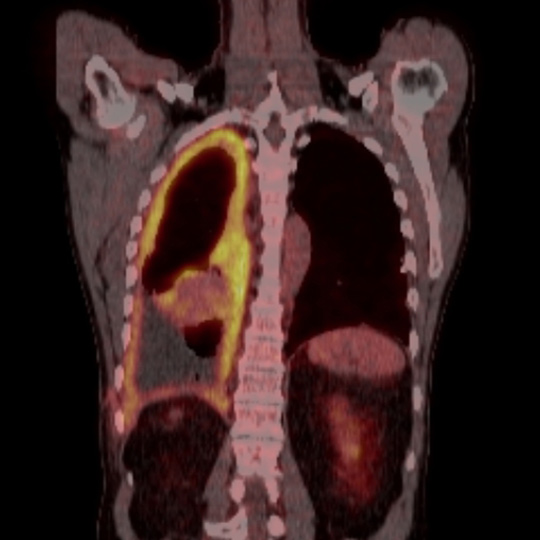

Typisk vekstmønster for malignt pleuralt mesoteliom

En mann i 60-årene ble utredet på bakgrunn av økende dyspné. Han hadde vært eksponert for asbest noen uker i 1970-årene, og hadde røykt fra 15 års alder. Det ble ikke funnet atypiske celler i pleuravæske. Diagnosen pleuralt mesoteliom ble fastsatt etter åpen pleurabiopsi. 18-fluorodeoksyglukose positronemisjonstomografi kombinert med computertomografi (18F-FDG PET/CT) ble rekvirert for å avklare om han kunne være kandidat for kirurgi.

18F-FDG tas opp i celler med høyt energibehov, som hjerte- og hjerneceller, betennelsesceller og maligne celler. Avbildning med PET/CT viser til venstre opptak i et malignt pleuralt mesoteliom med typisk utbredelse langs mesotelkledde hinner, her langs høyre pleura, inkludert lappespaltene. Til høyre viser CT alene de strukturelle forandringene i detalj, men skiller dårligere mellom viabelt tumorvev og benigne forandringer, som atelektase.

18F-FDG PET/CT gir mulighet for mer nøyaktig bestemmelse av sykdomsutbredelsen enn CT alene. Dette utnyttes blant annet til å selektere pasienter med begrenset sykdom for kirurgi. Ved pleurafortykkelse av ukjent årsak kan undersøkelsen være til hjelp i vurderingen av hvorvidt fortykkelsen skyldes malignitet. På grunn av lav oppløselighet har undersøkelsen imidlertid begrenset sensitivitet for små eller tynne maligne lesjoner (< 5 – 8 mm, avhengig av kamerateknologi). Tynne eller små maligne lesjoner i pleura inkludert i lappespalter kan derfor være PET-negative. Tykkere lesjoner uten opptak av 18F-FDG er mest sannsynlig benigne, selv om man må ta høyde for enkelte tumortyper som ikke tar opp stoffet.

Hos denne pasienten ble utbredelsen vurdert å være for omfattende til at kirurgi var aktuelt. Han ble behandlet med palliativ kjemoterapi med målsetting livsforlengelse og symptomkontroll.